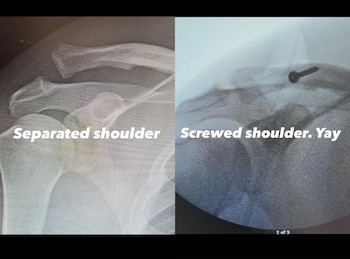

Horas después, Tatum dio más detalles sobre su estado de salud a través de Instagram Stories, donde publicó imágenes de radiografías de su hombro. En ellas hizo notar la lesión y, luego, la ubicación de un tornillo o clavo para el tratamiento correspondiente.